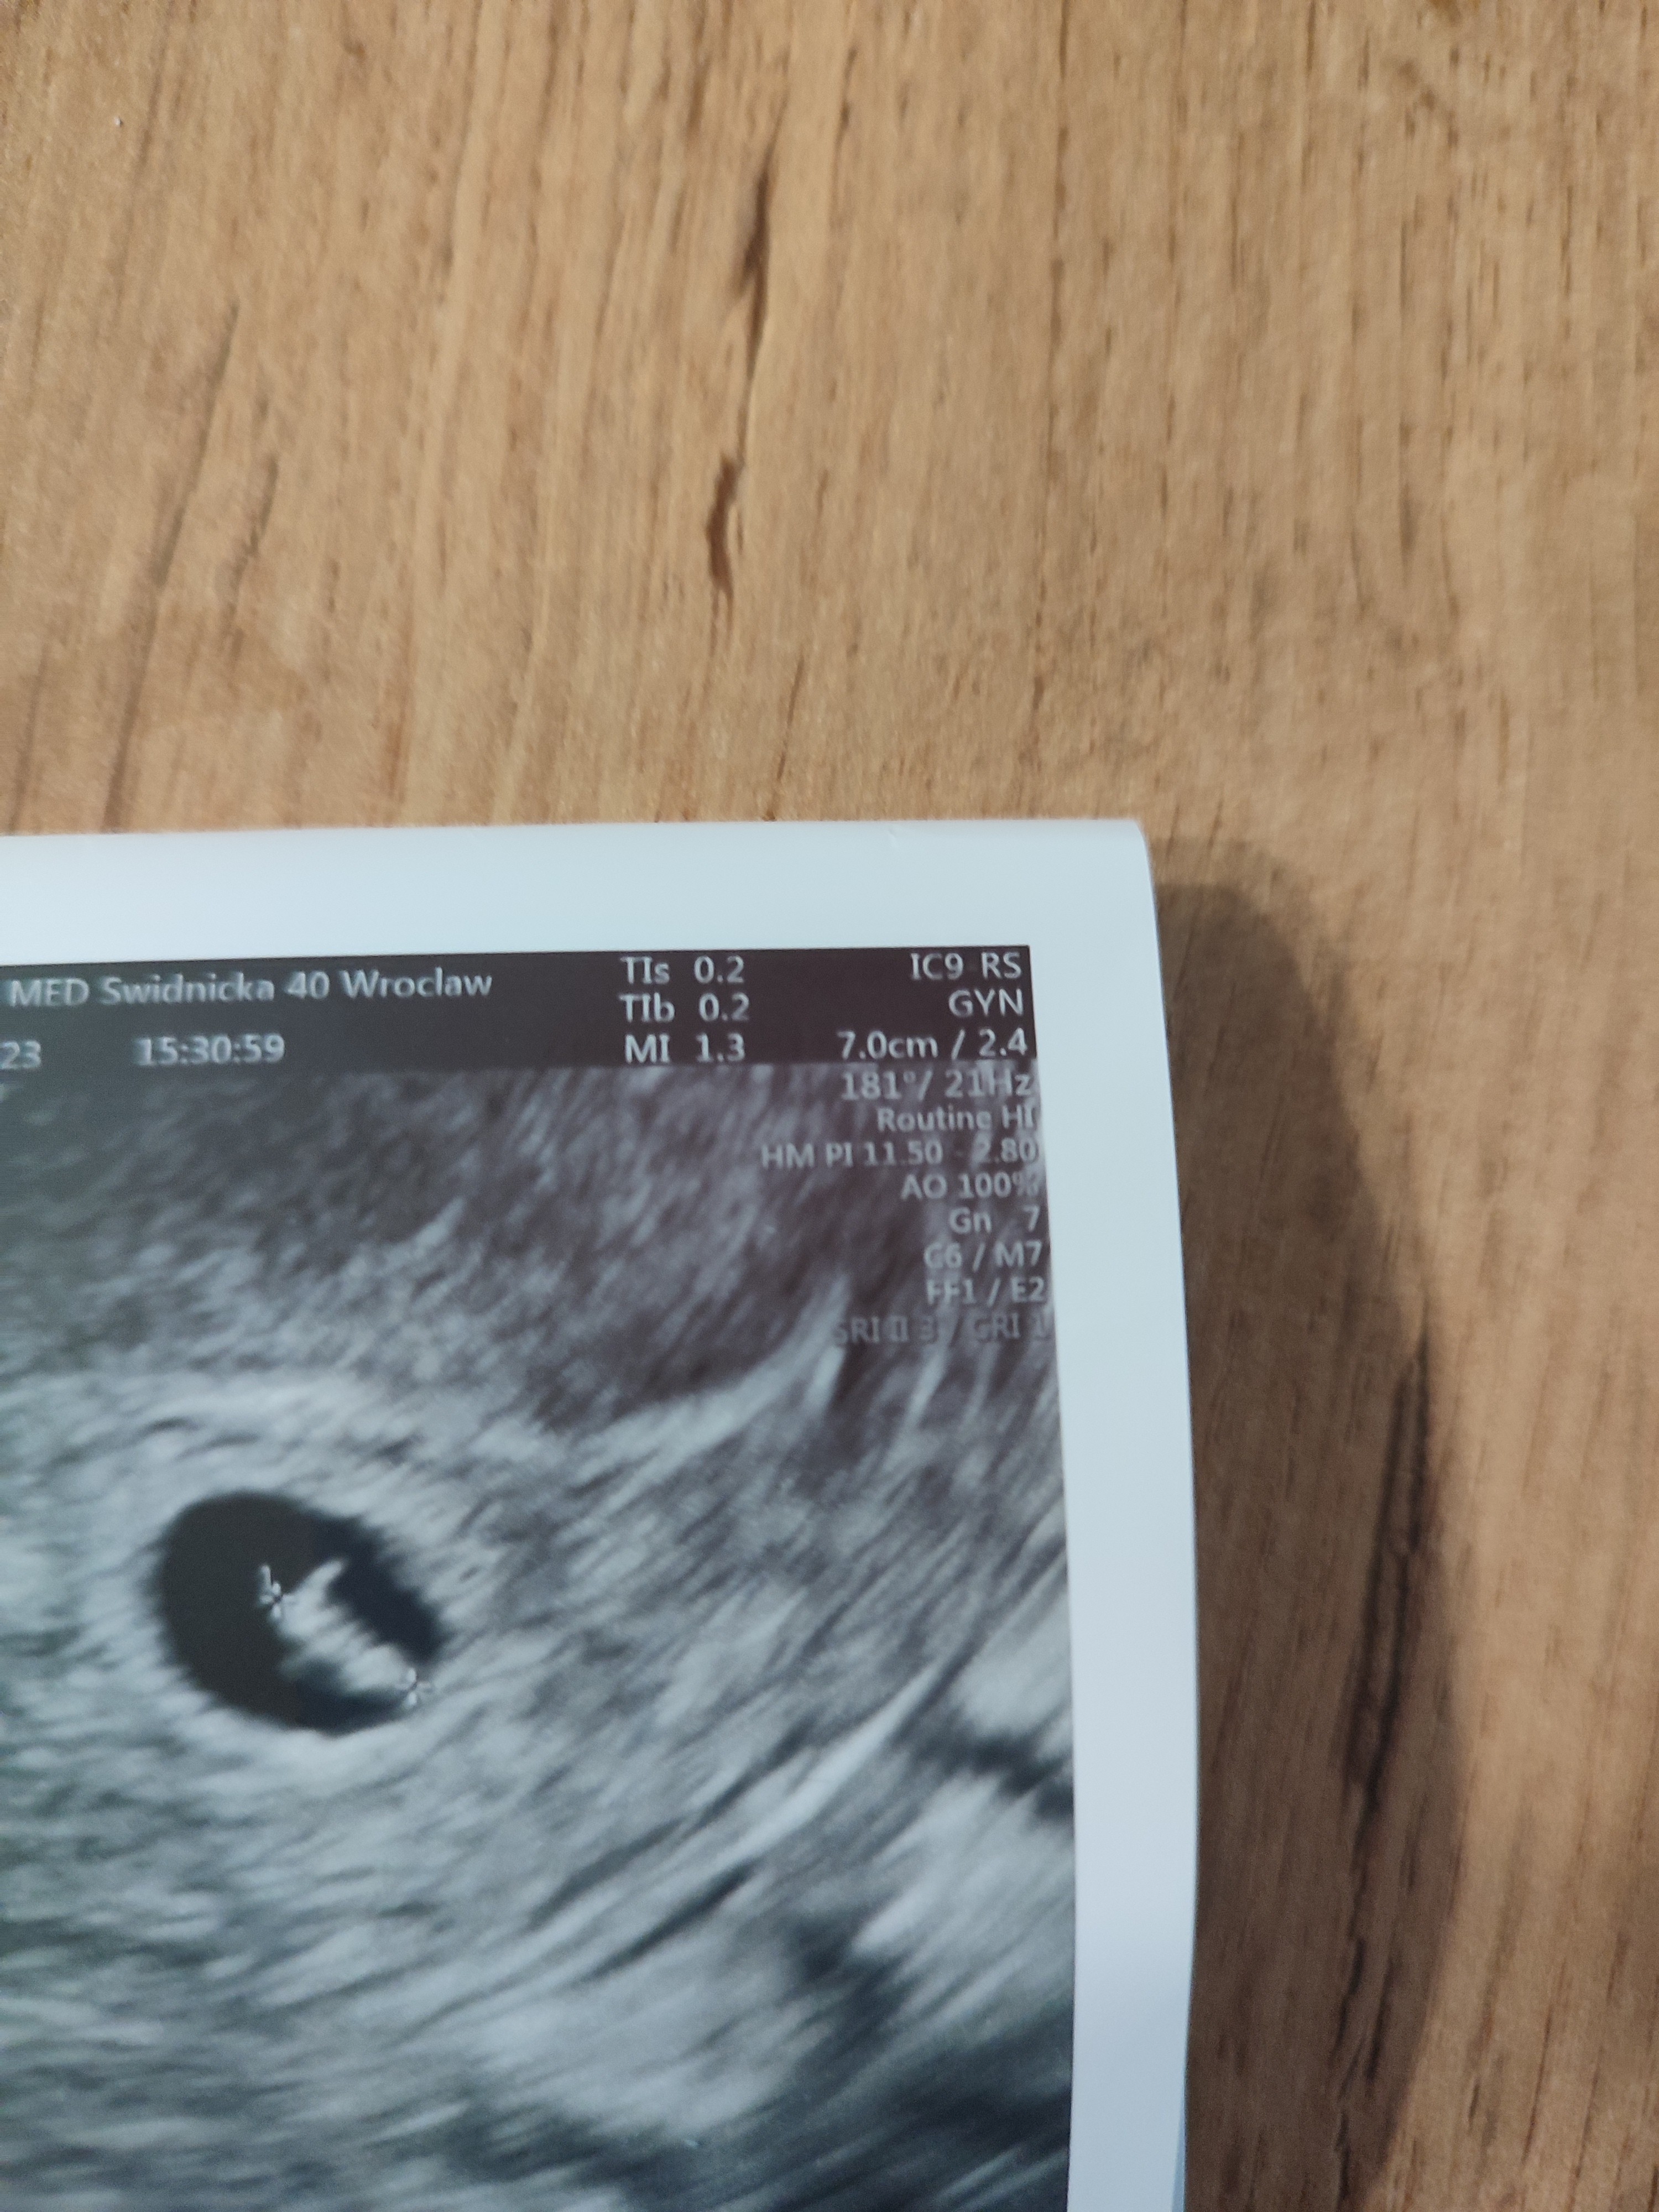

to nie są pomiary. To dane sprzętu usg. Pomiary są zwykle w którymś dolnym roguProszę![]()

Mam tylko wielkość zarodka, nic więcejto nie są pomiary. To dane sprzętu usg. Pomiary są zwykle w którymś dolnym rogu

ale dopiero może się rozkręcać bo to zawsze od „czegoś” startuje a nie odrazu szybko. Zarodek jeszcze mały i ma prawo być wolniejsze bicia serca. A kiedy nast wizyta? Jaki tydzien ciąży to będzie?0.52 cm i 6t+3 dni. Nie wskazała ile uderzeń serca, patrzyła na monitor i mówiła, że wolno.